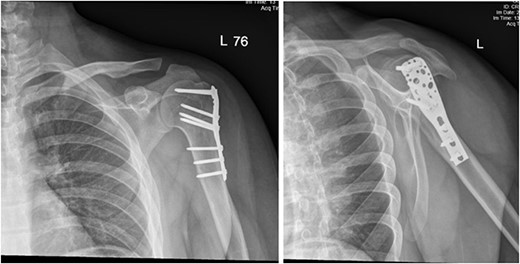

Upon arrival the patient underwent exploratory laparotomy followed by irrigation and debridement of both femur and humerus and application of external fixators (Fig. 2). The patient was admitted to the intensive care unit (ICU). Two days later, the patient underwent open reduction and internal fixation of both proximal and distal humerus (Fig. 3).

Anteroposterior (AP) view of the left humerus and elbow after ORIF.

The patient underwent left open reduction and internal fixation of proximal and distal humerus under general anesthesia. The patient was placed in the lateral position. Preparation and draping in the usual sterile manner were performed and a sterile tourniquet was used. The distal humerus was first approached through a posterior approach. Ulnar nerve protection and olecranon osteotomy was done, showing simple distal intraarticular fracture with minimal metaphyseal comminution. Anatomical reduction of the articular fracture was achieved, with preliminary fixation by k-wires holding the intra-articular fragments. This was followed by interfragmentary screw fixation from medial to lateral. Dual plate fixation (posterolateral and medial anatomical plates) was used to fix both medial and lateral columns, connecting the articular fragment to the metaphyseal. Reduction was confirmed under x-ray. Joint was tested for any screw penetration, and none was found. The osteotomized olecranon was reduced and fixed with cannulated screws and tension bands. The ulnar nerve was protected throughout the whole procedure and was reduced back into the cubital tunnel. Range of motion was examined; full range of motion was achieved. Finally, closure was done in layers.

The patient was then shifted from lateral to beach-chair position, and preparation and draping were repeated. A deltopectoral approach was utilized reaching to the proximal humerus. Reduction was achieved, followed by preliminary fixation with k-wires. Philos plates were used to fix the fracture. Range of motion was examined afterward, with no struggles detected. Fluoroscopic images were taken later to make sure no screws had penetrated the joint. Closure in layers was done, followed by dressing and application of an arm sling.